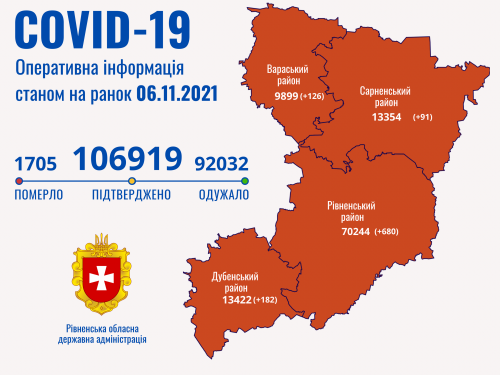

Пів тисячі - у важкому стані, 9 жителів Рівненщини померли за добу від коронавірусу